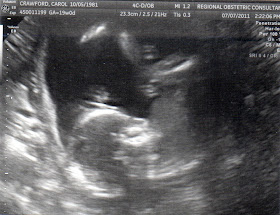

Last week, after returning from PA, we had our almost-20 week ultrasound to check on the baby and all is perfect! Two hands, two feet, saw the heartbeat and the spine and the belly and all that cute stuff!

Here's a photo of baby, looks like sucking its thumb!

And then, here's our acrobat! Feet up in the air, butt wiggling around, and head at the bottom. :-)